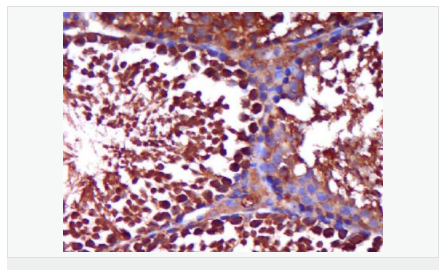

| 产品应用 | WB=1:500-2000 ELISA=1:5000-10000 IHC-P=1:100-500 IHC-F=1:100-500 Flow-Cyt=1ug/Test IF=1:100-500 (石蜡切片需做抗原修复) not yet tested in other applications. optimal dilutions/concentrations should be determined by the end user. |

| 产品介绍 | The androgen receptor gene is more than 90 kb long and codes for a protein that has 3 major functional domains: the N-terminal domain, DNA-binding domain, and androgen-binding domain. The protein functions as a steroid-hormone activated transcription factor. Upon binding the hormone ligand, the receptor dissociates from accessory proteins, translocates into the nucleus, dimerizes, and then stimulates transcription of androgen responsive genes. This gene contains 2 polymorphic trinucleotide repeat segments that encode polyglutamine and polyglycine tracts in the N-terminal transactivation domain of its protein. Expansion of the polyglutamine tract causes spinal bulbar muscular atrophy (Kennedy disease). Mutations in this gene are also associated with complete androgen insensitivity (CAIS). Two alternatively spliced variants encoding distinct isoforms have been described. [provided by RefSeq, Jul 2008] Function: Steroid hormone receptors are ligand-activated transcription factors that regulate eukaryotic gene expression and affect cellular proliferation and differentiation in target tissues. Transcription factor activity is modulated by bound coactivator and corepressor proteins. Transcription activation is down-regulated by NR0B2. Activated, but not phosphorylated, by HIPK3 and ZIPK/DAPK3. [ENZYME REGULATION] AIM-100 (4-amino-5,6-biaryl-furo[2,3-d]pyrimidine) suppresses TNK2-mediated phosphorylation at Tyr-267. Inhibits the binding of the Tyr-267 phosphorylated form to androgen-responsive enhancers (AREs) and its transcriptional activity. Subunit: Binds DNA as a homodimer. Part of a ternary complex containing AR, EFCAB6/DJBP and PARK7. Interacts with HIPK3 and NR0B2 in the presence of androgen. The ligand binding domain interacts with KAT7/HBO1 in the presence of dihydrotestosterone. Interacts with EFCAB6/DJBP, PELP1, PQBP1, RANBP9, RBAK, SPDEF, SRA1, TGFB1I1, ZNF318 and RREB1. Interacts with ZMIZ1/ZIMP10 and ZMIZ2/ZMIP7 which both enhance its transactivation activity. Interacts with SLC30A9 and RAD54L2/ARIP4. Interacts via the ligand-binding domain with LXXLL and FXXLF motifs from NCOA1, NCOA2, NCOA3, NCOA4 and MAGEA11. The AR N-terminal poly-Gln region binds Ran resulting in enhancement of AR-mediated transactivation. Ran-binding decreases as the poly-Gln length increases. Interacts with HIP1 (via coiled coil domain). Interacts (via ligand-binding domain) with TRIM68. Interacts with TNK2. Interacts with USP26. Interacts with RNF6. Interacts (regulated by RNF6 probably through polyubiquitination) with RNF14; regulates AR transcriptional activity. Interacts with PRMT2 and TRIM24. Interacts with GNB2L1/RACK1. Interacts with RANBP10; this interaction enhances dihydrotestosterone-induced AR transcriptional activity. Interacts with PRPF6 in a hormone-independent way; this interaction enhances dihydrotestosterone-induced AR transcriptional activity. Interacts with STK4/MST1. Interacts with ZIPK/DAPK3. Interacts with LPXN. Interacts with MAK. Part of a complex containing AR, MAK and NCOA3. Subcellular Location: Nucleus. Cytoplasm. Note=Predominantly cytoplasmic in unligated form but translocates to the nucleus upon ligand-binding. Can also translocate to the nucleus in unligated form in the presence of GNB2L1. Tissue Specificity: Isoform 2 is mainly expressed in heart and skeletal muscle. Post-translational modifications: Sumoylated on Lys-386 (major) and Lys-520. Ubiquitinated. Deubiquitinated by USP26. 'Lys-6' and 'Lys-27'-linked polyubiquitination by RNF6 modulates AR transcriptional activity and specificity. Phosphorylated in prostate cancer cells in response to several growth factors including EGF. Phosphorylation is induced by c-Src kinase (CSK). Tyr-534 is one of the major phosphorylation sites and an increase in phosphorylation and Src kinase activity is associated with prostate cancer progression. Phosphorylation by TNK2 enhances the DNA-binding and transcriptional activity and may be responsible for androgen-independent progression of prostate cancer. Phosphorylation at Ser-81 by CDK9 regulates AR promoter selectivity and cell growth. Phosphorylation by PAK6 leads to AR-mediated transcription inhibition. Palmitoylated by ZDHHC7 and ZDHHC21. Palmitoylation is required for plasma membrane targeting and for rapid intracellular signaling via ERK and AKT kinases and cAMP generation. DISEASE: Defects in AR are the cause of androgen insensitivity syndrome (AIS) [MIM:300068]; previously known as testicular feminization syndrome (TFM). AIS is an X-linked recessive form of pseudohermaphroditism due end-organ resistance to androgen. Affected males have female external genitalia, female breast development, blind vagina, absent uterus and female adnexa, and abdominal or inguinal testes, despite a normal 46,XY karyotype. Defects in AR are the cause of spinal and bulbar muscular atrophy X-linked type 1 (SMAX1) [MIM:313200]; also known as Kennedy disease. SMAX1 is an X-linked recessive form of spinal muscular atrophy. Spinal muscular atrophy refers to a group of neuromuscular disorders characterized by degeneration of the anterior horn cells of the spinal cord, leading to symmetrical muscle weakness and atrophy. SMAX1 occurs only in men. Age at onset is usually in the third to fifth decade of life, but earlier involvement has been reported. It is characterized by slowly progressive limb and bulbar muscle weakness with fasciculations, muscle atrophy, and gynecomastia. The disorder is clinically similar to classic forms of autosomal spinal muscular atrophy. Note=Caused by trinucleotide CAG repeat expansion. In SMAX1 patients the number of Gln ranges from 38 to 62. Longer expansions result in earlier onset and more severe clinical manifestations of the disease. Note=Defects in AR may play a role in metastatic prostate cancer. The mutated receptor stimulates prostate growth and metastases development despite of androgen ablation. This treatment can reduce primary and metastatic lesions probably by inducing apoptosis of tumor cells when they express the wild-type receptor. Defects in AR are the cause of androgen insensitivity syndrome partial (PAIS) [MIM:312300]; also known as Reifenstein syndrome. PAIS is characterized by hypospadias, hypogonadism, gynecomastia, genital ambiguity, normal XY karyotype, and a pedigree pattern consistent with X-linked recessive inheritance. Some patients present azoospermia or severe oligospermia without other clinical manifestations. Similarity: Belongs to the nuclear hormone receptor family. NR3 subfamily. Contains 1 nuclear receptor DNA-binding domain. SWISS: P10275 Gene ID: 367 Database links: Entrez Gene: 367 Human Entrez Gene: 11835 Mouse Omim: 313700 Human SwissProt: P10275 Human SwissProt: P19091 Mouse Unigene: 496240 Human Unigene: 39005 Mouse Unigene: 394224 Mouse Unigene: 439657 Mouse Unigene: 9813 Rat Important Note: This product as supplied is intended for research use only, not for use in human, therapeutic or diagnostic applications. AR是一个由917个氨基酸组成的蛋白质,位于雄激素靶组织细胞中或细胞表面上的特异分子部位或结构。 AR在前列腺癌中起着重要的作用,研究表明AR的表达与组织分型形成一定的相关性 ,AR在高分化的肿瘤中表达较多,而在低分化的肿瘤中表达较少。用于前列腺癌的检测,指导临床治疗,目前可用于乳腺癌、食道癌等各项肿瘤的研究。 |